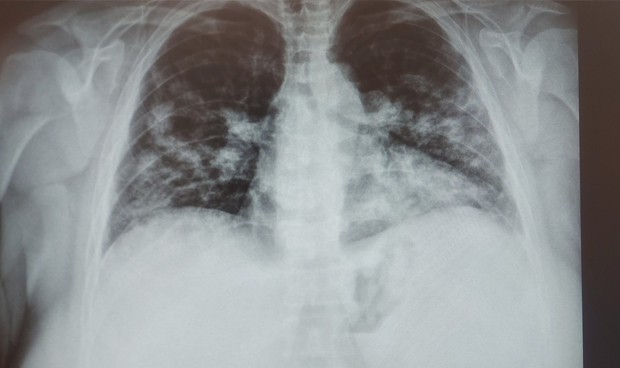

Covid-19 segunda ola: "Hacía meses que no veía una radiografía así"

Los facultativos coinciden en la incidencia de la segunda ola de Covid-19 y continúan alertando de las consecuencias que tiene este virus en la población. Es el ejemplo de una médica de Familia que ha reconocido que desde hace meses no mandaba al hospital a un paciente con una radiografía así.

"Así lo empezamos a hacer en marzo, un paciente con disnea, inestable o saturación muy baja, ni me lo planteo, a urgencias de cabeza. Un paciente dudoso, Rx y si no hay neumonía, para casa. Mientras los radiólogos de mi centro, no me digan lo contrario, seguiremos actuando así", aclara está médica.